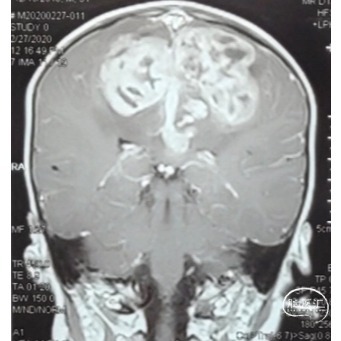

双侧额顶叶中线旁脑实质内团片状异常信号影,呈明显花环状强化,累积脑膜及胼胝体压部,性质待定,恶性胶质瘤?

本例患儿肿瘤位于双侧额顶叶,大脑镰旁,增强扫描呈明显环形强化,提示肿瘤血运丰富。患儿年龄小,体重低,相对血容量少,如何控制术中出血是手术成功的关键。而术后肢体瘫痪或瘫痪加重是手术的主要并发症,中央沟静脉损伤、胼周动脉损伤、中央沟局部皮层损伤、癫痫、血肿以及脑水肿加重是其常见原因。术前脑血管造影有助于判断肿瘤与周围血管、组织的位置关系,明确上失状窦有无闭塞,对手术的切口设计有重要的参考价值及避免术中损伤不易发现的血管及组织。

非典型畸胎瘤样/横纹肌样瘤( AT /RT) 是发生在儿童中枢神经系统的少见的具有极大侵袭性的恶性肿瘤,在儿童中枢神经系统肿瘤中发病率极低。CT平扫多表现为混杂密度,也可等或稍高密度,呈不均匀或均匀强化,瘤内常可见囊性变及瘤周低密度水肿带。MRI扫描T1加权像为低信号,T2加权像为等信号或高信号,肿瘤实质与灰质信号相似或稍高,增强扫描可见中等至明显 增强,等信号时可能与肿瘤细胞密集,细胞核比例大而含水量相对较少有关。AT /RT是原发于中枢神经系统、好发于儿童、极其少见、侵袭性极高的胚胎性肿瘤,临床表 现及影像学无特异性,确诊有赖于组织病理。最大限度的安全切除,并辅以放化疗,可改善患者预后,但总体预后仍然很差。